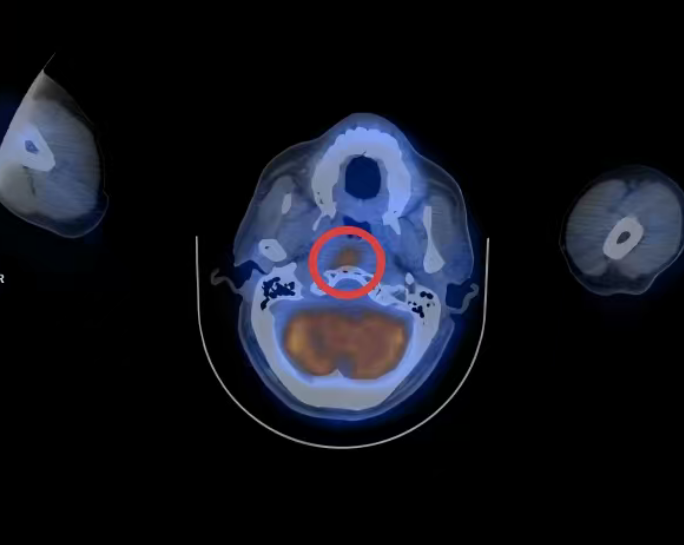

患者为74岁男性,既往接受鼻咽癌根治性放射治疗。本次随访复查MRI提示:右侧椎前间隙出现软组织结节,并侵犯头长肌;PET-CT高度怀疑肿瘤转移。

面对这一棘手问题,我院迅速启动多学科会诊机制。耳鼻咽喉头颈外科与呼吸与危重症医学科专家深入讨论后,提出突破性方案——借助超声支气管镜(EBUS)经鼻腔,对鼻咽后壁深部病灶实施实时影像引导下针吸活检。

术中依托超声支气管镜实时成像系统,动态显示病灶位置及周围血管结构,实现穿刺路径可视化。

在精准导航下,穿刺针准确进入MRI所示可疑结节区域,同时有效避开重要血管和神经结构,大幅提升操作安全性与取材成功率。